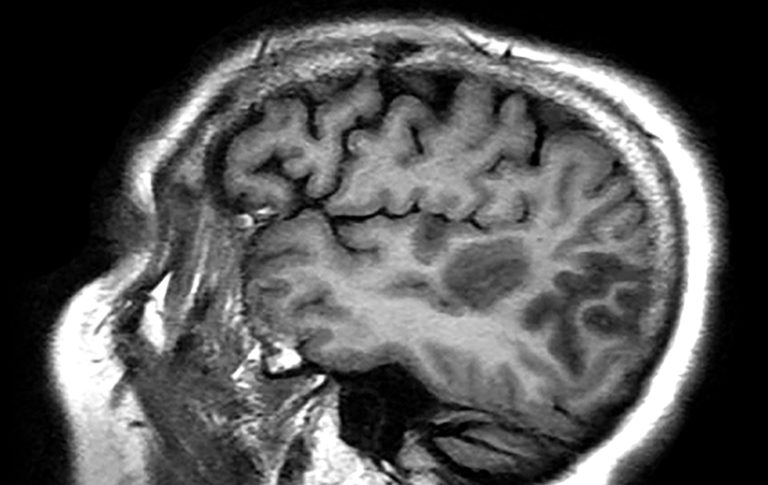

Maternal SARS-CoV-2 Infection Linked to Neurodevelopmental Diagnoses

Improving Pediatric Stroke Diagnosis: Filling the GapsBecause of the relative rarity of stroke in children, many clinicians tend to presume that mimics are the cause of the symptoms.